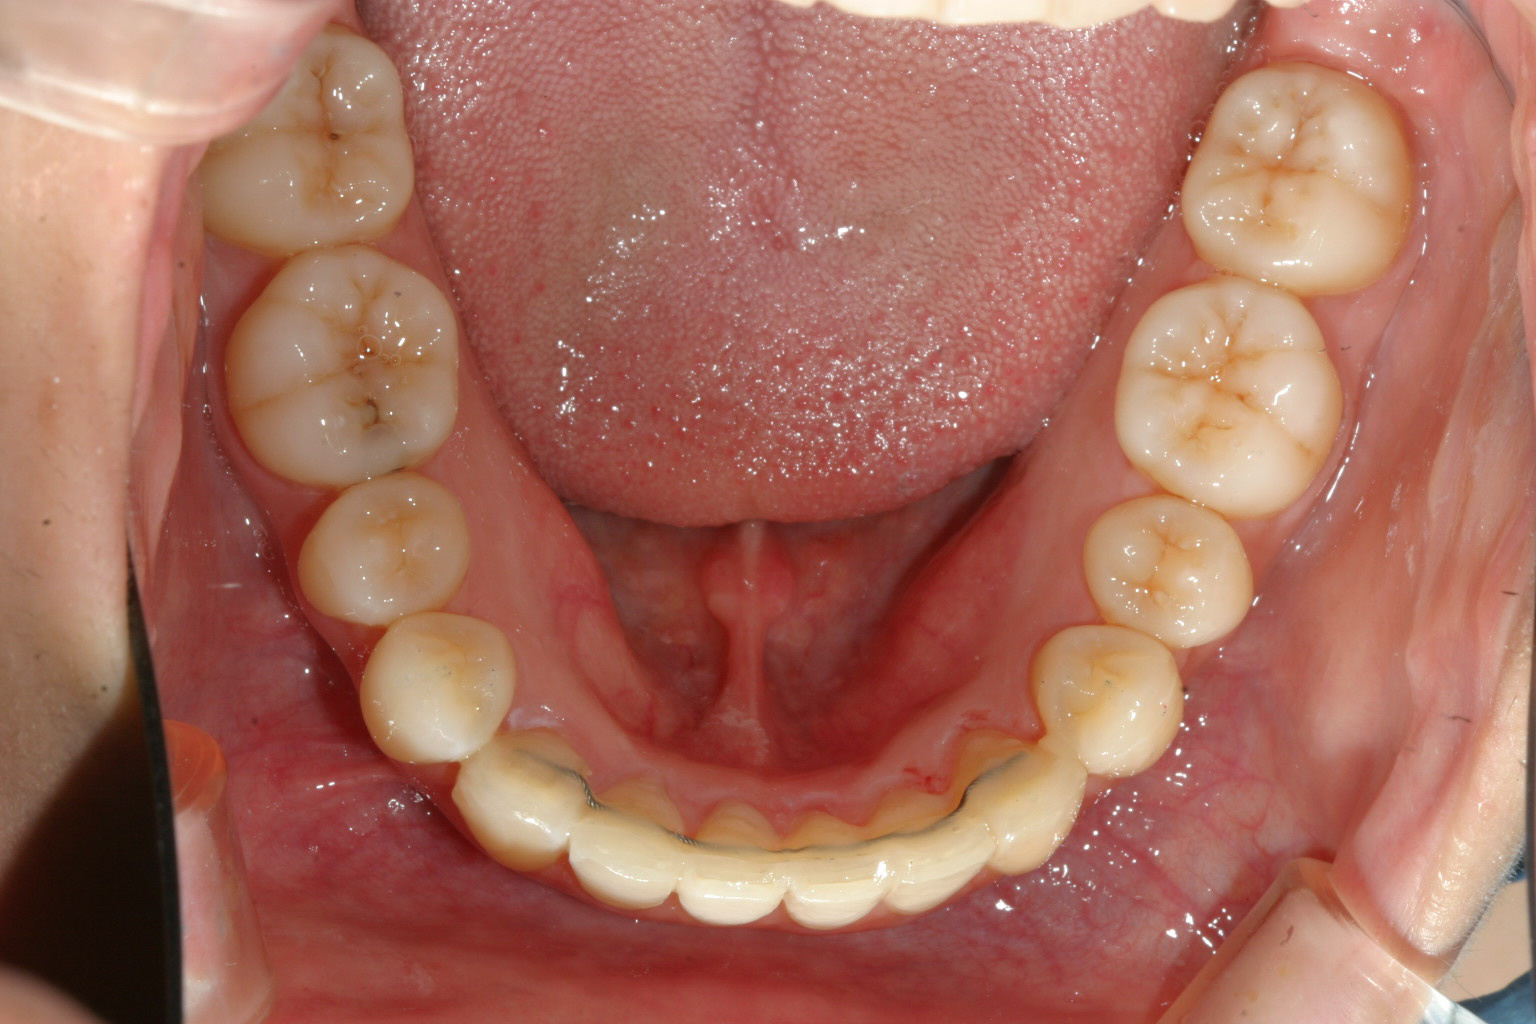

綺麗な歯並びが得られました。

下顎も凄い綺麗です。 beforeと比べてください。 U字形になってるのが分かります。 つまり犬歯と犬歯の間が開いたと言う事です。

オーバージェットもオーバーバイトも完璧です。